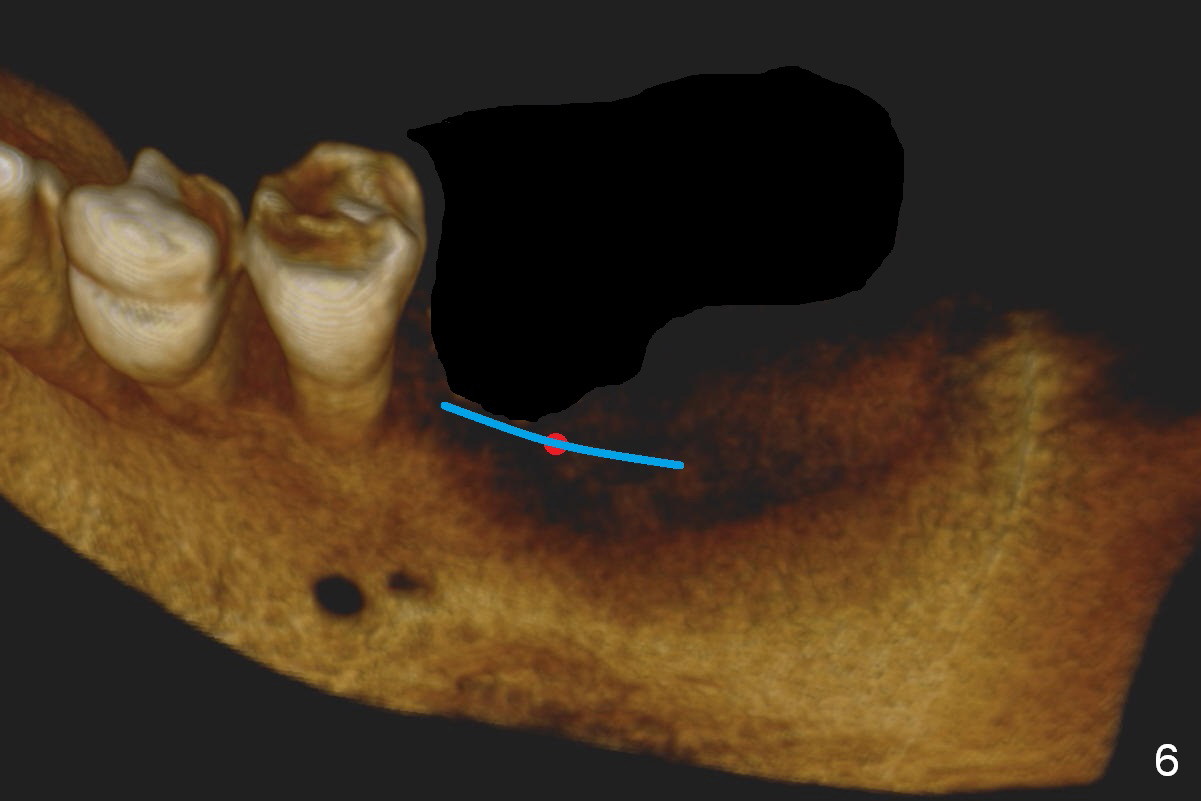

CBCT 3-D image taken with scan stents at the sites of #18 and 19 shows 2 Mental Foramina (Fig.1 *) in the left mandible.  Both sagittal (Fig.2) and coronal (Fig.3) sections show low density at the crest of #19 of a 55-year-old man (arrowheads).  The crest is also narrow.  After making an initial osteotomy through the stent (Fig.4 red arrow), remove the latter (Fig.5).  Ridge split is initiated with wheel saws (Fig.6 blue line).  The osteotomy is enlarged with bone expanders (Fig.7 green circle) with ridge split (blue lines).  Finally an implant is placed (Fig.8 pink circle) with placement of bone graft in the space of the ridge split (yellow circles).